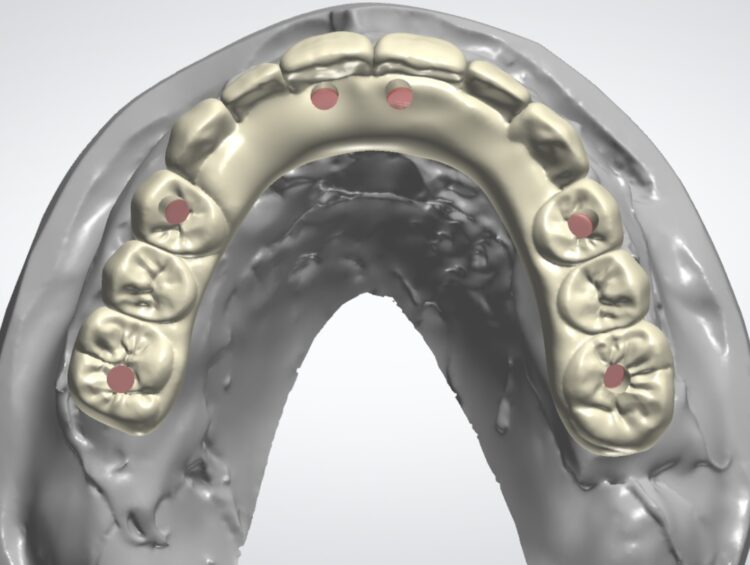

When ready, the surgical planning involved a fully digital, prosthetically-driven workflow, with full dentist and dental technician collaboration. Intraoral scans (IOS) were merged with the DICOM data from the CBCT to optimise data capture and facilitate an accurate digital plan for implant placement and prosthesis design. The digital files and photographs were imported into a Digital Design Software (EXOCAD) and a personalised, facially-driven tooth library was used to perform an initial virtual wax-up.

The use of a surgical guide for the accurate and precise placement of the dental implants was chosen in this case. The positions and angulations of the implants were planned according to the ideal virtual wax-up that was produced. We decided to create a tooth-supported acrylic guide for fully guided surgery, supplemented by bone-fixed anchor pins for enhanced stability. The most appropriate teeth for this were identified during this planning phase.

The design of the provisional prosthesis followed the Gallucci prosthetic guide protocol[i] providing a 3D printed composite bridge with palatal support. The palatal support sits below the fitting surface of the bridge and is only used to locate the bridge in centric occlusion using the hard palate of the patient. This bridge is an exact copy of the digital wax-up used to plan the implant positions. The use of guided surgery guarantees that the implants are placed precisely according to the plan.

The provisional restoration in this case had prefabricated prosthetic channels to match the same planned implant positions and angulations. This provisional was located in the mouth using the hard palate and attached on the titanium cylinders that penetrate through the bridge, with the use of a composite based light cured material.